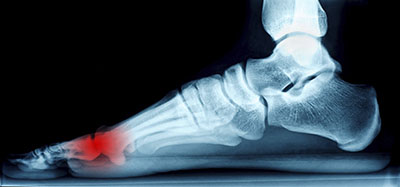

The Plantar Fascia is a strong ligament structure (tensile strength of 4000 lb/sq. inch) that helps to maintain the structure and arch of the foot. It extends from the base of the toes to the heel bone or calcaneus bone.

The Plantar Fascia is almost as wide as the foot and plays an important role in the support of the foot.

Plantar Fasciitis is the condition caused by overuse or injury. When the Plantar Fascia is strained due to overuse, improper shoes, or poor foot structure it gets irritated and tender. The resulting inflammation causes the symptoms of pain that include: a burning sensation on the sole of the foot, and recurring foot pain especially after getting out of bed in the morning or sitting.

Long standing inflammation can cause the formation of calcium deposits at the point where the plantar fascia inserts into the heel bone or along the course of the plantarfascia. The spur itself is not actually the cause of pain.

The Achilles tendon is a major tendon that attaches the calf muscle to the heel bone. Achilles tendonitis occurs as pain and inflammation at the back portion of the heel, at the insertion of the Achilles tendon. It may also cause a bursitis often associated with a "pump bump", or Haglund's deformity. A sore bump may be present on either side of the heel at the insertion of the tendon. X-rays will often show a bone enlargement or spur with calcification inside the tendon. Treatment is aimed at reducing the pressure and inflammation to the area through the use of heel cups, heel lifts, orthotics, padding, medication and physiotherapy. Cortisone injections are not recommended in this area due to their potential to cause tendon rupture. The Achilles tendon can also become enlarged and show a fusiform swelling due to micro tears within the tendon. This is known as tendinopathy.